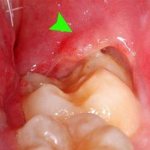

It often happens that after tooth extraction, the patient experiences swelling of the gums and swelling. There is no need to worry - this is a normal reaction of the gums after surgery. To reduce discomfort, place something fairly cold under your cheek on the side where the tooth was removed. Regular ice will do for this. Hold it on the sore spot for ten minutes, rest for twenty minutes and hold it again for ten minutes. The swelling will go down and will no longer bother you.